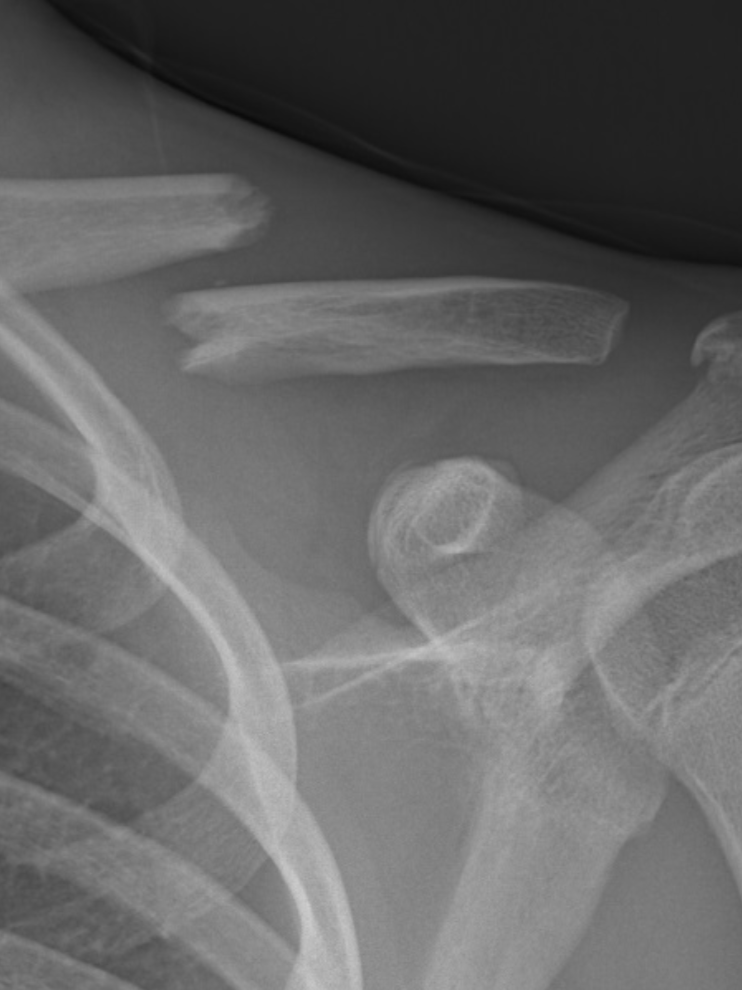

Acromio-Clavicular Dislocation

Clavicular Fracture